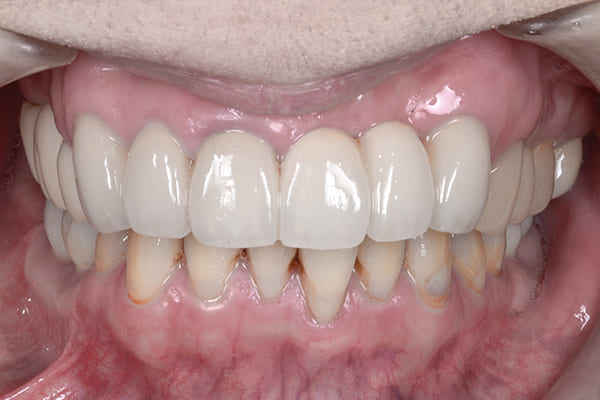

治療前後の比較

このように横に並べると変化がよくわかります。

治療を通じて、患者様の笑顔がより自然で明るくなり、自身を持って笑えるようになったことをとても嬉しく思います。